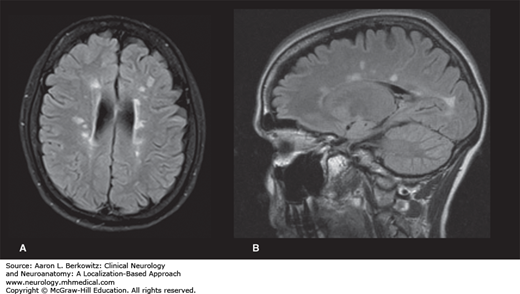

Neuroimaging of MS

- Key diagnostic test for MS

- Classic radiologic features of MS are small, ovoid T2/FLAIR hyperintensities that are perpendicularly oriented to the lateral ventricles and corpus callosum.

- Acute lesions may demonstrate enhancement with gadolinium, often in an open ring (as compared to the complete ring of contrast enhancement seen with tumor and abscess)

- The damage caused by lesions over time can lead to T1 hypointensities at sites of prior demyelination (T1 black holes).